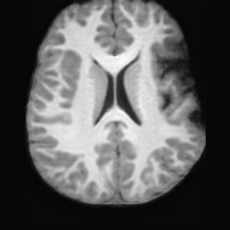

(a)PathologicalInput ImageSynthSR [18]Brain-ID [28]UNA [30]USBHealthyGround TruthRefer to captionRefer to captionRefer to captionRefer to captionRefer to captionRefer to captionRefer to captionRefer to captionRefer to captionRefer to captionRefer to captionRefer to captionRefer to captionRefer to captionRefer to captionRefer to captionRefer to captionRefer to captionRefer to captionRefer to captionRefer to captionRefer to captionRefer to captionRefer to caption(b)HealthyInput ImageConditionalLesion MaskUNA [30]USBRefer to captionRefer to captionRefer to captionRefer to captionRefer to captionRefer to captionRefer to captionRefer to captionRefer to captionRefer to captionRefer to captionRefer to captionRefer to captionRefer to captionRefer to captionRefer to caption

Figure 5: Comparison of bidirectional brain editing. (a) pathology-to-healthy, the circles and arrows highlight lesion regions and unsuccessful reconstructions; (b) healthy-to-pathology. Note that SynthSR and Brain-ID cannot perform healthy-to-pathology editing.

Pathology-to-Healthy Editing. Fig. 5 (a) presents comparison results on four input brain images with lesions of varying sizes, shapes, and densities. All competing models, although specialized for healthy brain image synthesis, struggle to reconstruct pathological regions, especially near lesion boundaries. In contrast, USB accurately reconstructs the corresponding healthy brain, even in challenging cases with large, high-density lesions where normal brain structures are almost completely obscured (last row). Tab. 2 provides a quantitative comparison for pathology-to-healthy editing, where USB achieves the best performance across all three datasets, demonstrating the effectiveness of its unified framework in reconstructing healthy brains from pathological inputs. Additional results are in Suppl. B.